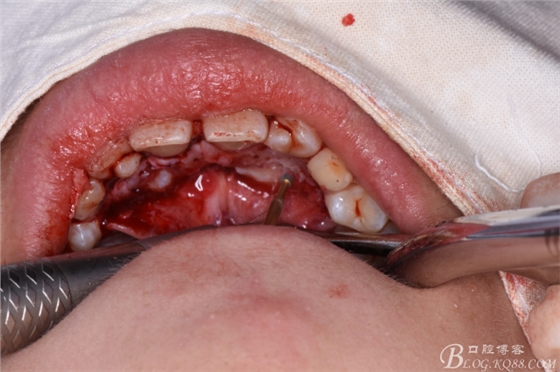

圖5.行腭側(cè)齦溝內(nèi)的水平切口

圖6.切口從13腭側(cè)至23腭側(cè)。

圖7.翻13腭側(cè)至23腭側(cè)瓣、暴露腭側(cè)骨面

圖8.弧形骨鑿去骨、初步找到13、23牙冠點(diǎn)